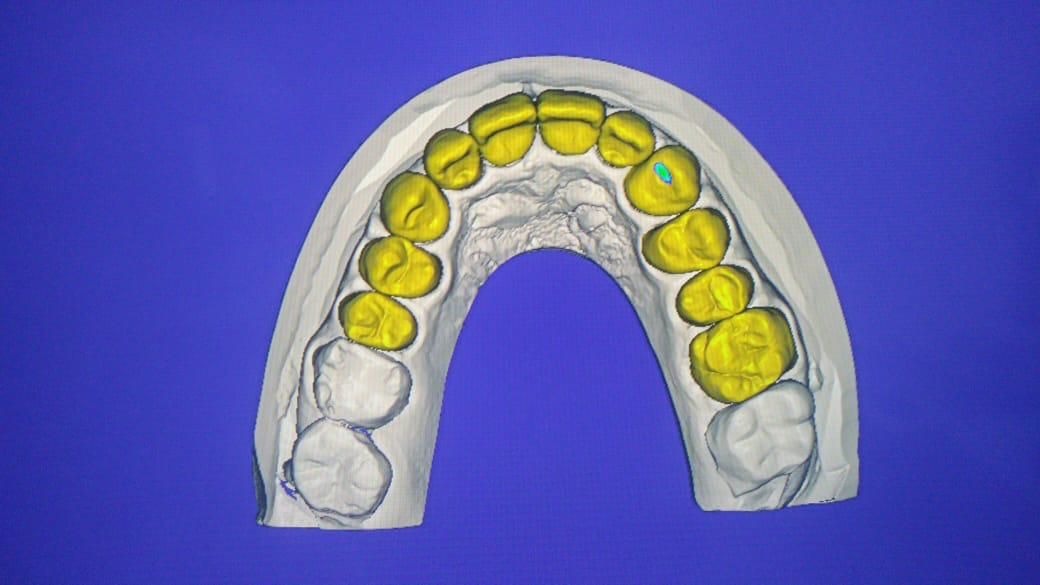

Especialista en prótesis bucal fija y removible, cédula de especialidad 13216976

La especialidad en prótesis Bucal se enfoca en rehabilitar mediante prótesis unitarias, múltiples o totales la función masticatoria de nuestros pacientes brindándoles una mejor estética dental, confort, anatomía dental y función.

Contamos con tecnología de punta que nos facilitara el diagnostico y tratamiento de tu problema dental lo cual hará mas predecible el éxito a largo plazo.